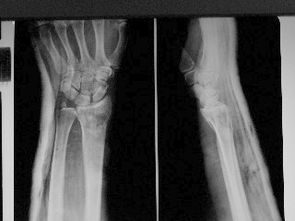

術(shù)者用兩手觸摸骨折部位,根據(jù)X 線片所顯示的骨折類型和移位情況,分別采用反折、回旋,端提、捺正和分骨、扳正等手法予以復(fù)位。